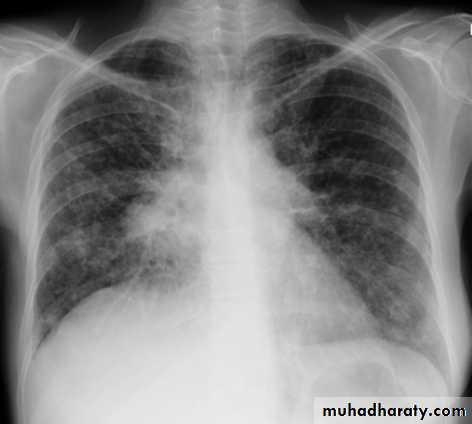

Cardiothoracic ratio (CTR) = Cardiac Width : Thoracic Width

A CTR of greater than 1:2 (50%) is considered abnormal. This however, assumes the projection is Posterior-Anterior (PA), and that cardiac size is not exaggerated by factors such as patient rotation or an incomplete breath in .

The cardiothoracic ratio aids in the detection of cardiomegaly, or more broadly, HYPERLINK "http://radiopaedia.org/articles/enlargement-of-the-cardiac-silhouette" enlargement of the cardiac silhouette.

Enlargement of the cardiac silhouette on chest x-ray can be due to a number of causes :

cardiomegaly (most common cause by far)pericardial effusion